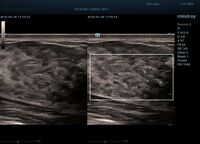

HD Scope позволяет достигать поразительной разрешающей способности выбранной зоны сканирования, при этом улучшая как детализацию, так и контрастность изображения. Помимо пространственного разрешения мы получаем преимущество и по разрешению во времени. Прибор получает огромное количество нативных изображений практически одновременно, и при сборе итоговой картины не происходит смещения объекта под датчиком, а значит и нет размывания изображения. Все участки раздела фаз, каждый контур образования теперь видны, мы все ближе к идеальной картинке.